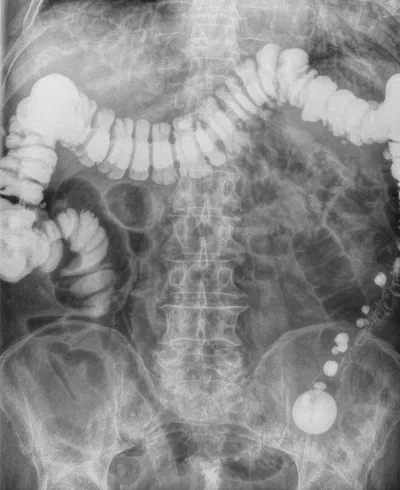

Un lavement baryté est un examen radiologique permettant d'étudier le rectum et le côlon.

Il consiste à injecter un produit de contraste opaque aux rayons X, la baryte, dans le rectum et le côlon du patient, via une petite canule introduite dans l'anus. Puis des clichés radiographiques de l'abdomen sont pris.

Cet examen permet de détecter des tumeurs, polypes, diverticules, inflammations et infections.